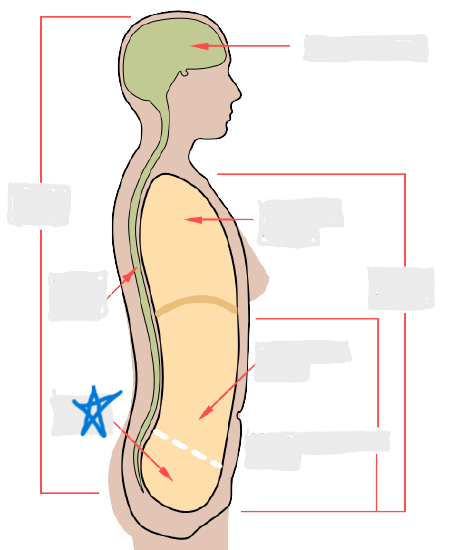

axial

cephalic

occipital

frontal

otic

orbital

nasal

oral

mental

cervical

dorsal

scapular

vertebral

lumbar

sacral

gluteal

thoracic

sternal

mammary

axillary

abdominal

umbilical

pelvic

inguinal

pubic

perineal

appendicular

acromial

brachial

antecubital

olecranal

antebrachial

carpal

manus

coxal

femoral

patellar

popliteal

crural

sural

peroneal

calcaneal

plantar

dorsal/posterior

ventral/anterior

lateral

medial

distal

proximal

superficial

deep

superior

inferior

cranial cavity

vertebral cavity

pleural cavity

pericardial cavity

mediastinum

abdominal cavity

pelvic cavity